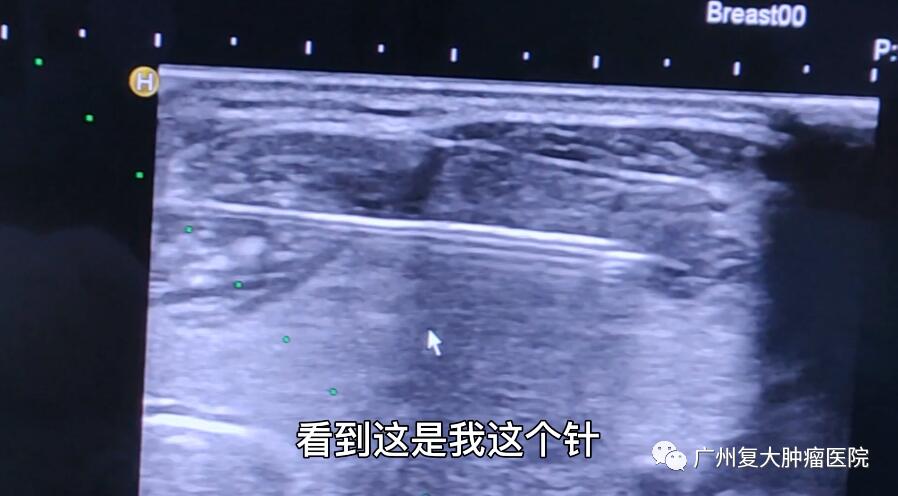

入院3天后,刘女士在完善治理前准备后接受了治疗。在B超引导下,牛立志院长用细针行穿刺活检,送术中快速病理检查,结果提示良性病变,穿刺病理:(右侧)甲状腺细针穿刺细胞学涂片中未查见癌细胞。得知良性结果后,牛立志院长通过微波消融术为其减少肿瘤体积,缓解肿瘤对患者呼吸道的压迫。

“患者的甲状腺肿越长越大,逐渐出现气管压迫、呼吸和吞咽困难的症状。她自身不想接受开刀手术,这种情况微波消融是一个很好的选择。”牛立志院长说道,由于患者甲状腺肿巨大,且双侧多发结节,在消融过程中需要足够的耐心,同时要分区域一步步进行消融。“整个过程就一个针眼。”